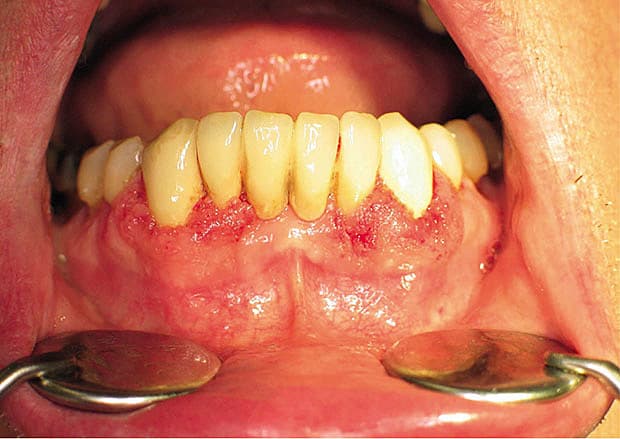

En 61-årig mand med gingivitis omkring incisiver og hjørnetænder i underkæben blev fra en privatpraktiserende tandlæge henvist til Tandlægeskolen. På baggrund af det karakteristiske udseende, strawberry gums, og en biopsi, som viste inflammation med eosinofile granulocytter og småabscesser, men dog ingen granulomer, vaskulitis eller kæmpeceller, blev der rejst mistanke om granulomatose med polyangiitis. Værdierne for C-reaktivt protein (CRP), antineutrofile cytoplasmatiske antistoffer (ANCA) og urinstiks var alle normale, og rinoskopi og røntgenoptagelse af thorax viste ligeledes normale forhold. Tilstanden gik i ro alene på to ugers prednisolonbehandling.

Granulomatose med polyangiitis kan debutere som isoleret gingivitis, hvor der først senere tilkommer involvering af andre organer, f.eks. som her øvre og nedre luftveje samt nyrer.